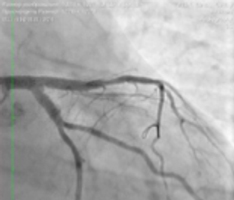

— Мы приняли решение о проведении эндоваскулярной коррекции этого поражения. С помощью двух баллоных катетеров диаметром 2,5 мм была выполнена предварительная дилатация стеноза ствола левой коронарной артерии, устьев огибающей артерии и передней нисходящей артерии по методике «целующихся баллонов». Это одновременное раздувание двух баллонов на бифуркации — успешно применяемое нами прогрессивное техническое новшество. Затем выполнено стентирование по методу culotte с выходом в переднюю нисходящую и огибающую артерии. На контрольной ангиограмме был выявлен критический стеноз в проксимальной трети передней нисходящей артерии, который ранее был маскирован основным поражением. Был стентирован участок в проксимальной трети. На контрольной ангиограмме кровоток в левой коронарной артерии по шкале TIMI — III, что означает оптимальный результат стентирования. Зон диссекций и резидуальных стенозов нет.

![]() Ангиографический результат коррекции |

Через 2 дня пациент был выписан, боли не рецидивировали. А через неделю сообщил, что вернулся к занятиям спортом.